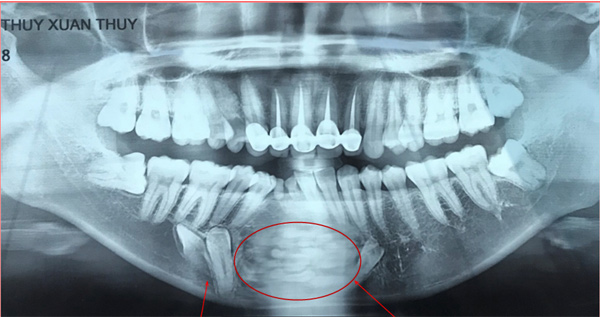

Chính vì thế, rất nhiều bệnh nhân điều trị sai cách, loại bỏ u không triệt để, dẫn tới bệnh tiến triển ngày một nặng dẫn tới gãy xương hàm, đứt dây thần kinh,.. U răng rất khó phát hiện, chỉ qua phim chụp X-quang mới có thể nhìn thấy.

Hình ảnh u răng được phát hiện qua phim chụp X-quang

Vừa qua tại Nha khoa bệnh viện thẩm mỹ JW Hàn Quốc đã tiếp nhận điều trị cho một nữ nhân viên văn phòng mắc bệnh u răng. Theo các bác sĩ răng hàm mặt tại bệnh viện JW, khối u đã xuất hiện từ rất lâu phía hàm răng dưới của bệnh nhân, do không được điều trị kịp thời nên các mầm răng trong khối u phát triển ngày một lớn. Bác sĩ JW sau nhiều giờ phẫu thuật đã lấy ra gần 40 chiếc răng li ti từ khối u của bệnh nhân.